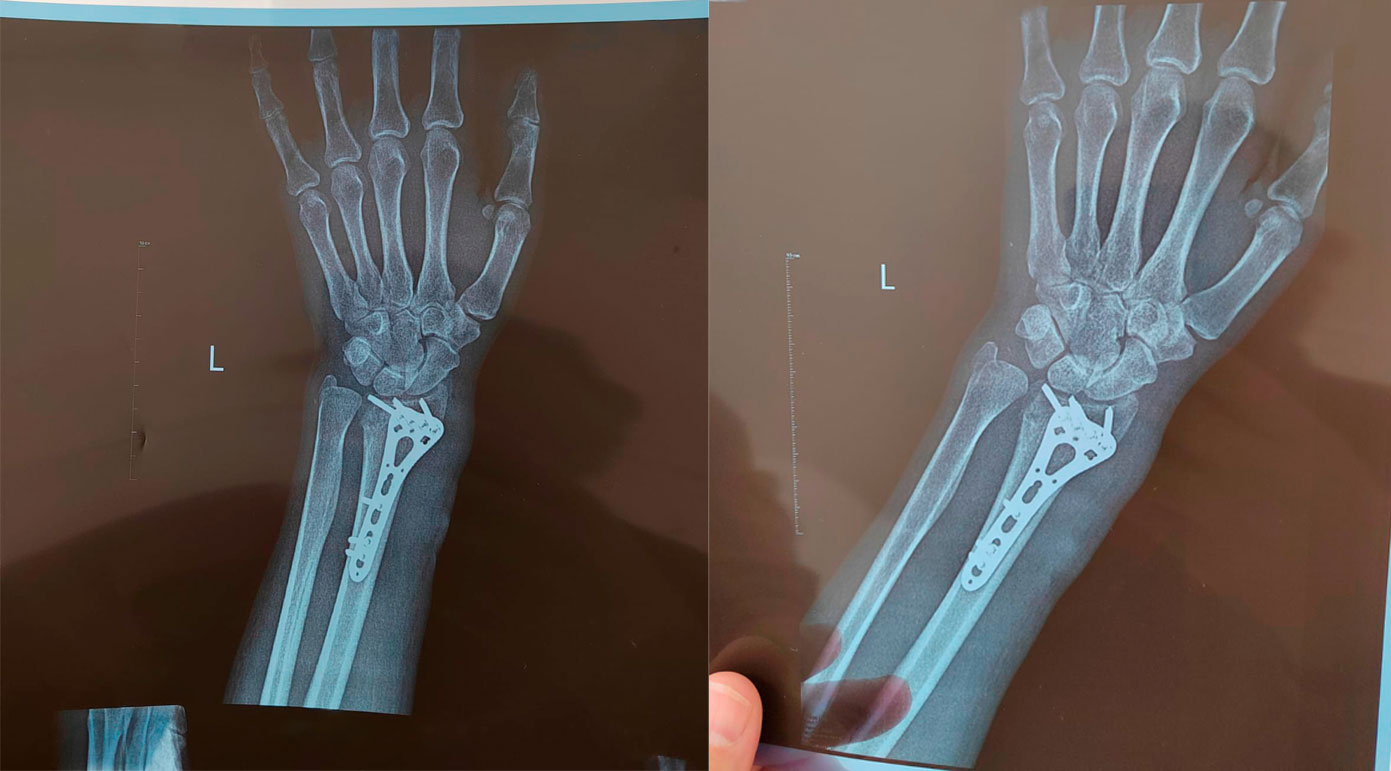

Остеосинтез – это хирургическая операция, цель которой – надежно зафиксировать сломанные кости и создать идеальные условия для их правильного и быстрого сращения. Наиболее часто используют остеосинтез при нестабильных оскольчатых переломах длинных трубчатых костей и внутрисуставных переломах.

Суть остеосинтеза — фиксация костных обломков специальной металлоконструкцией. Так кость срастается быстро, надежно и в анатомически правильном положении.